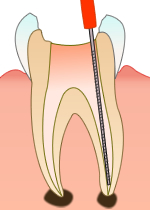

「根管治療」とは、歯の神経(歯髄)の治療のことです。

虫歯が悪化して歯髄まで達している場合や、ケガなどで歯髄を損傷した場合などは、歯髄が腐敗しないように歯の神経をとる処置が必要です。その際、根管をきれいにし、根の先まで薬をつめる処置がきちんと行われないと、後々歯髄が化膿して、歯の根元に膿の袋ができたり痛みを引き起こします。